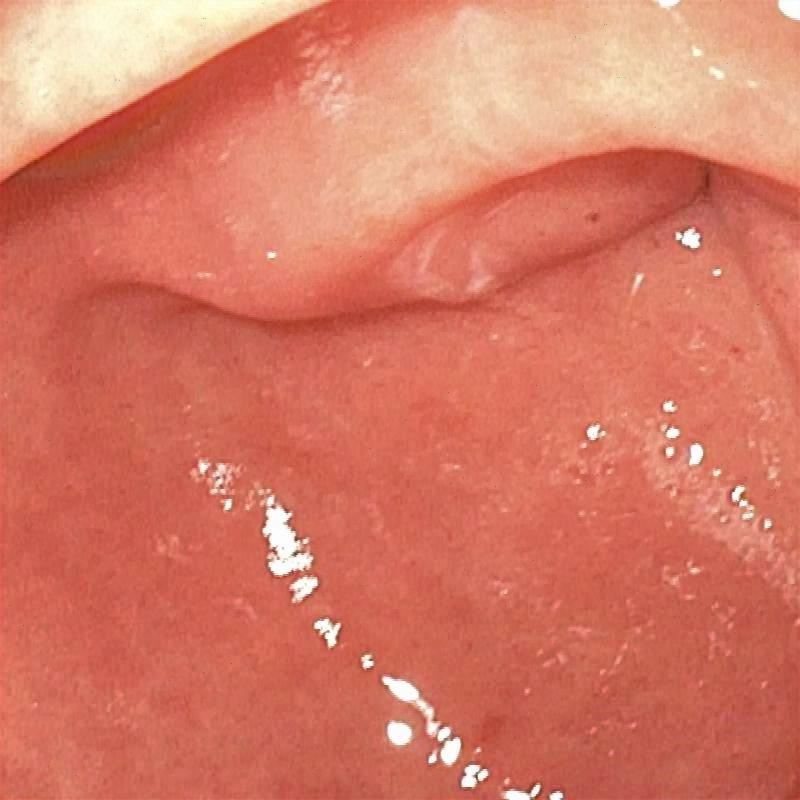

The proposed method was evaluated on a synthetic dataset. All deep learning-based methods were fine-tuned based on E-kvasri. Figure 2 presents sample results of the proposed method and comparative methods on four endoscopic images from the E-kvasri.

| (a) Input | (b) LIME | (c) HDRNet | (d) LECCM | (e) SwinIR | (f) NAFNet | (g) EndolMLE | (h) Ours | (i) GT |

| (PSNR/SSIM) | (19.83/0.9198) | (16.25/0.7606) | (12.21/0.5074) | (16.61/0.7913) | (29.40/0.9784) | (20.68/0.9277) | (27.19/0.9722) | (/1) |

| (PSNR/SSIM) | (18.98/0.9041) | (24.08/0.7885) | (12.80/0.4619) | (24.61/0.8472) | (25.09/0.9838) | (20.23/0.9045) | (35.54/0.9821) | (/1) |

| (PSNR/SSIM) | (15.58/0.9433) | (18.70/0.8041) | (12.60/0.5067) | (19.63/0.8192) | (18.40/0.9594) | (14.96/0.8328) | (33.33/0.9812) | (/1) |

| (PSNR/SSIM) | (14.61/0.8990) | (21.51/0.6768) | (12.06/0.3324) | (22.40/0.8726) | (22.60/0.9787) | (18.20/0.8649) | (27.64/0.9802) | (/1) |